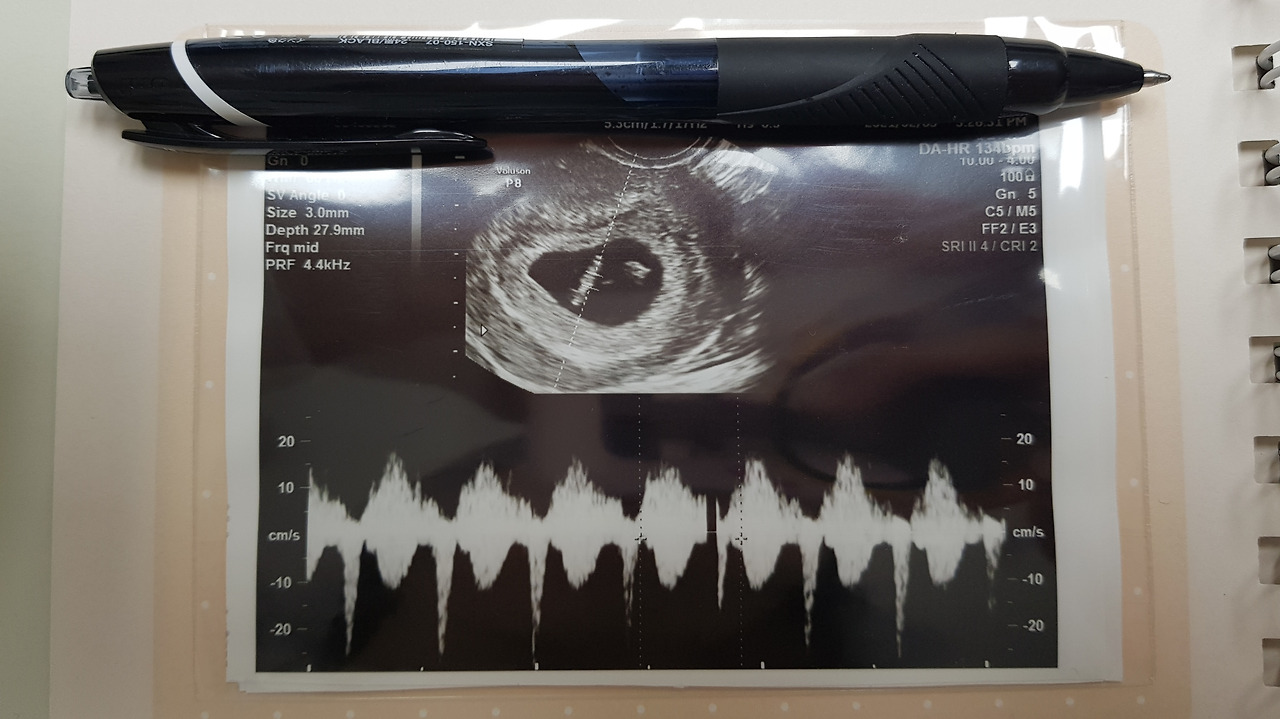

2주 만에 만난 덕순이는

내 걱정이 무색할 정도로 건강했다.

그전까지

내가 본 것은 아기가 아니라

아기집과

난황인데,

진짜 아기 덕순이는

그날에서야 처음 본 것이다.

아주 조그만 강낭콩 같은 덕순이 가운데에

반짝반짝

심장이 보였다.

134 bpm으

로 쉬지 않고 심장이 뛰고 있었다.

어른들의 심장 박동의 두 배가 되는 속도였다.

처음으로 듣는 덕순이의 심장 소리는

씩씩하고 우렁찼다.